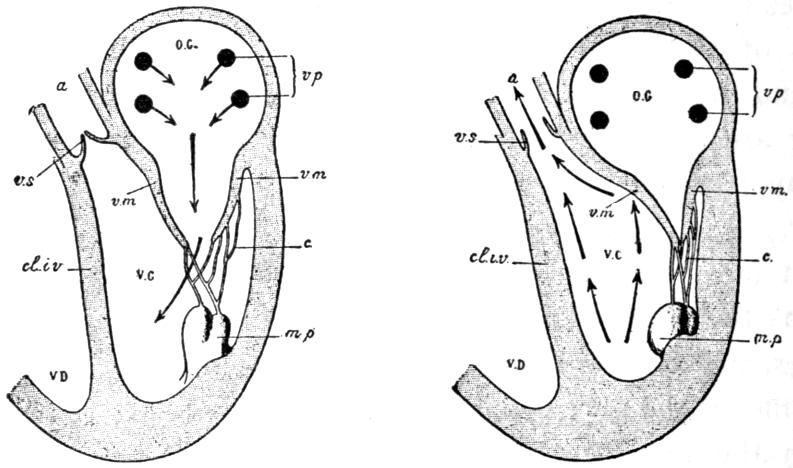

| V. | The Circulation | H 51 |